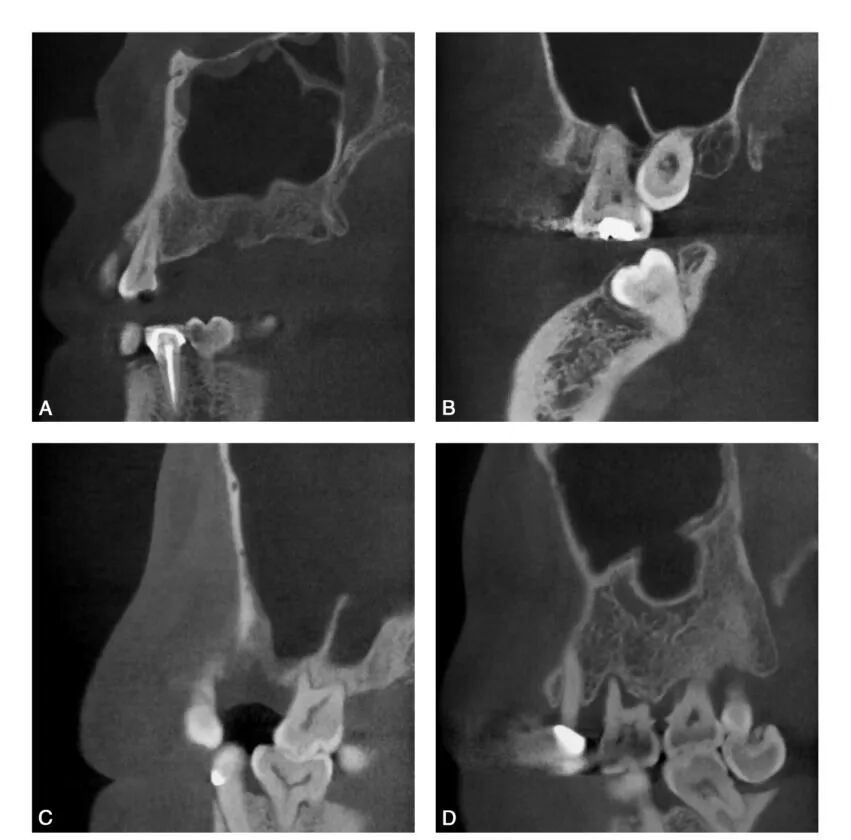

CBCT图像显示上颌窦是一个形状不规则,大小也不尽相同的腔,矢状位上是一由上、下、前、后壁构成的类似四方形或者梯形结构(图1-1-12)。冠状位上可见上颌窦上、下、内、外壁,形态多不规则(图1-1-13)。水平位可见前外、后外、内壁,中份多为类三角形,两端形态多不规则(图1-1-14)。上颌窦腔的容积为9. 5~20ml,平均为14. 75ml。不同人上颌窦形状和大小差别较大,同一个体双侧上颌窦形态基本对称(图1-1-15),但也存在同一个体两侧上颌窦形状和大小有差异(图1-1-16)。

CBCT矢状位示上颌窦形状不规则,类似四方形或者梯形结构

CBCT冠状位可见上颌窦上、下、内、外壁,窦腔形态不规则

A、C.可见窦腔形态不规则; B.窦腔形态类似三角形